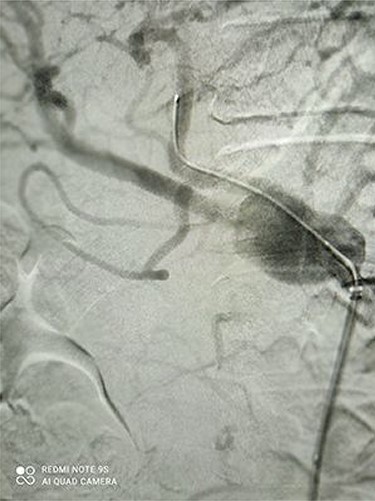

Figures 1 and 2 depict CAA in 3D images of CT angiography and angiography, respectively.